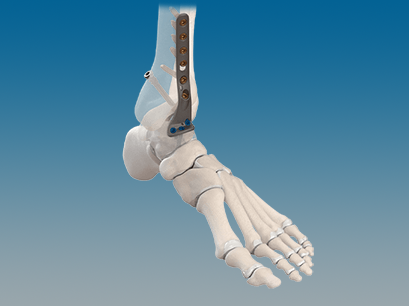

CONMED Foot and Ankle offers tailored innovation and simplified solutions. Explore our complete portfolio of arthroplasty, biologic, fixation, implant, suture anchor, and instrumentation offerings for foot and ankle surgery.

QUANTUM® Total Ankle System with OrthoPlanify™ Patient Specific Instrumentation